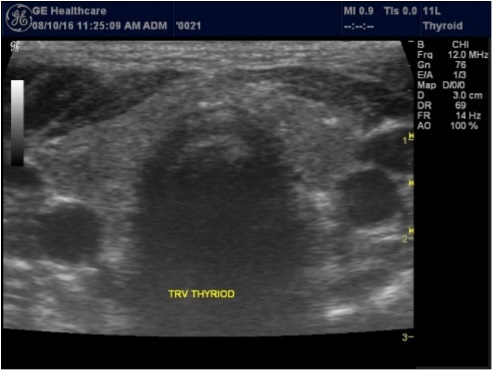

The superficial location of the thyroid gland renders it ideal for ultrasound examination 8. High resolution grey scale images can easily be obtained using high frequency transducer. In the transverse view, normal thyroid gland has the butter fly appearance, with left and right lobes connected with a narrow isthmus, Figure 1A. Both lobes can be imaged separately in the longitudinal plan, Figure 1B

Figure 1A.Normal thyroid gland transverse view